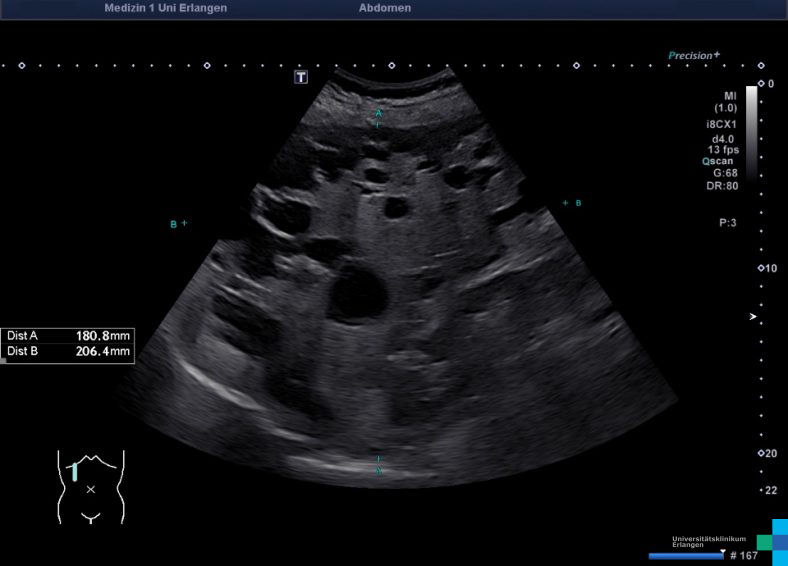

LEB_BEN_ZYL_1278.jpg